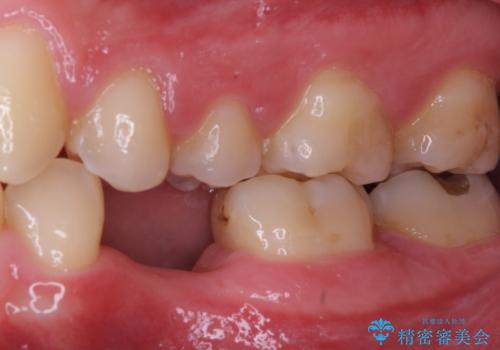

なお、反対側も永久歯先天欠如による、乳歯の残存がありますが、特に齲蝕も認められないため処置をせず、できるだけ保存していくこととしました。